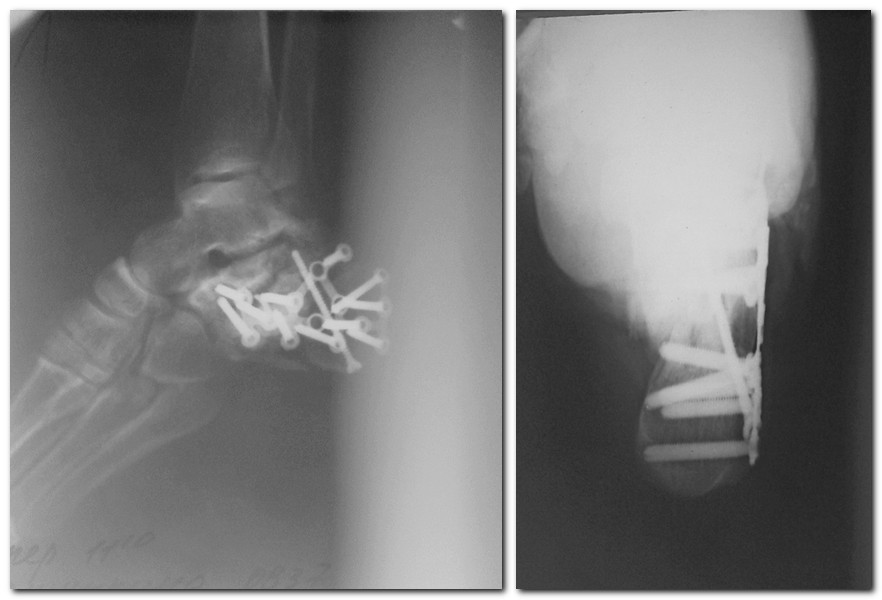

Спасибо за активное обсуждение. Прооперировали 2 недели назад с пластиной LCP и винтами, Chronos. Заживление проблемное. Сохраняется скудное серозное отделяемое. Швы сегодня сняли. По техническим причинам не получается выложить послеоперационные снимки. Как только, так сразу выложу.

В отделении ранее активно применялся накостный остеосинтез переломов пяточной кости. Про шкалу Андрея Анатольевича Волны (ABCDEF) мы тогда не знали (думаю, что могли бы иметь меньшее количество осложнений). Но осложнений было много. Частая причина – краевые некрозы кожных лоскутов и подлоскутные гематомы. Мало привлекательно, когда после снятия швов из раны длительно подбегает серозная жидкость или видна пластина.

- Конечно, открытая репозиция с фиксацией пластиной при корректном исполнении позволяет и ликвидировать смещение суставной поверхности, и восстановить форму. При хорошем качестве кости пластина при небольшом количестве внутрисуставных фрагментов (а здесь два крупных отломка) может быть как традиционной, так и блокированной. В последнем случае пластика дефекта совершенно необязательна. Да и с традиционной пластиной этого можно избежать при известных хирургических навыках

В данном случае имеются три крупных отломка, промежуточный фрагмент ушёл вниз, а пяточный бугор сместился кнаружи и "укоротился" - сместился кпереди, ну и, конечно, сместился краниально. Такой перелом достаточно просто репонируется закрыто с последующей фиксацией спицами (Патент №2368341 «Способ лечения переломов пяточной кости». Приоритет изобретения 04.09.2006 г. Жуков П.В., Стельмах К.К.). Кстати, Купитман сделал диссертацию - технология та же. Главное - результаты очень даже хорошие.